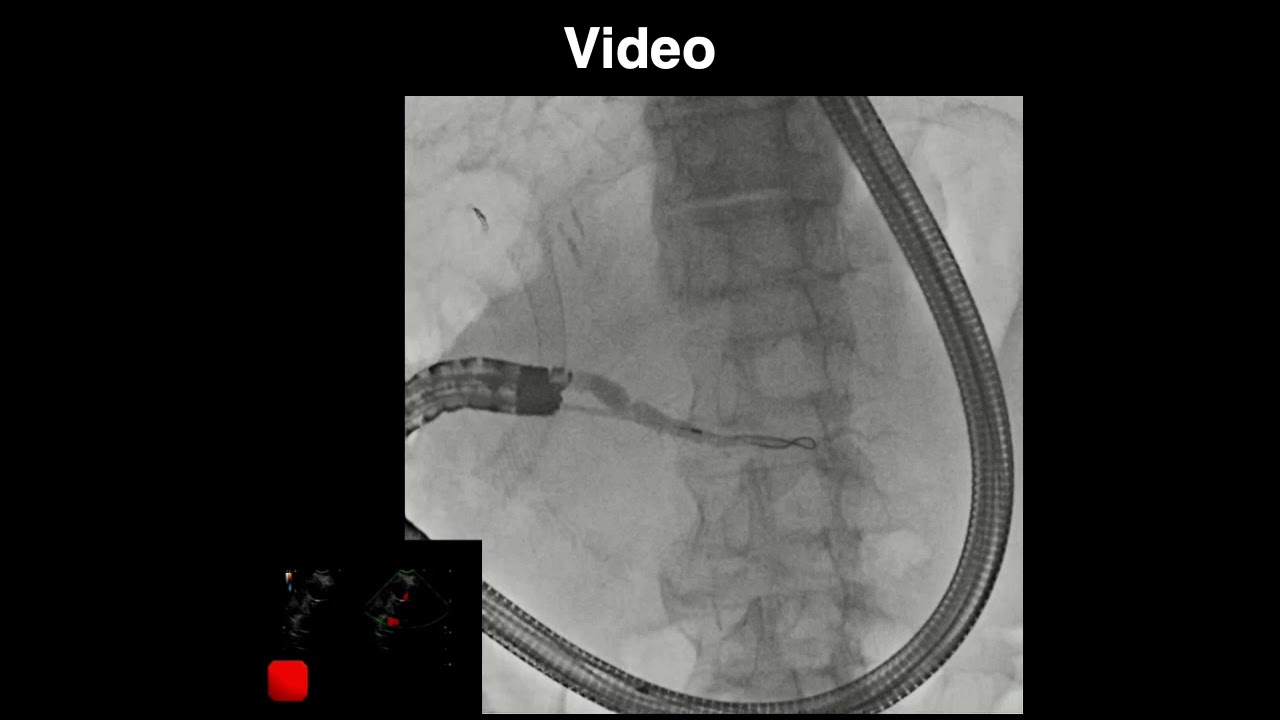

Endoscopic ultrasound-guided pancreaticoduodenostomy with a forward-viewing echoendoscope

Описание: Shigenobu Yoshimura, MD, et al, demonstrate EUS-guided pancreaticoduodenostomy with a forward-viewing echoendoscope in this video case report.

DOI: https://doi.org/10.1016/j.vgie.2021.0...